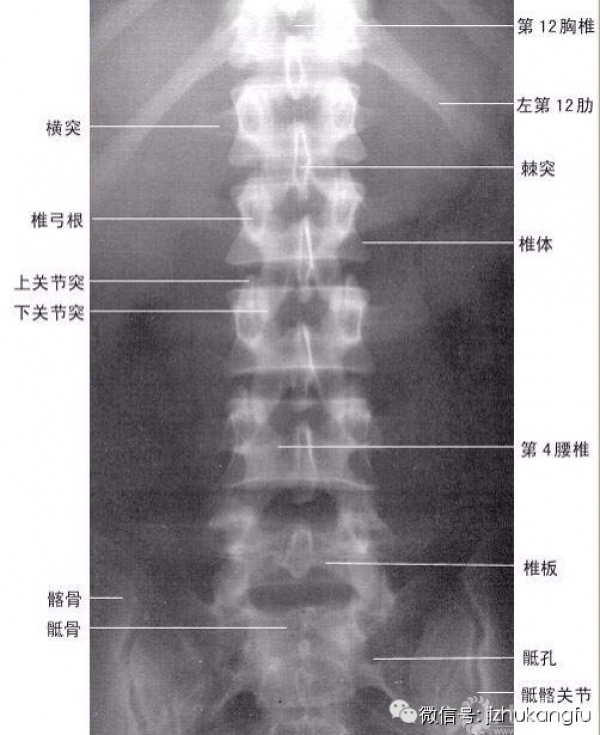

3腰椎